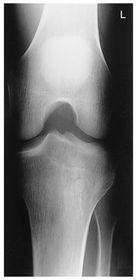

A. medial and lateral intercondylar tubercles B. lateral epicondyle femur C. lateral condyle femur D. lateral condyle tibia E. articular facets tibia (tibial plateau) F. medial condyle tibia G. medial condyle femur H. medial epicondyle femur I. patella

AP Knee pt supine w/ leg rotated internally 5 degrees to get knee in TRUE AP - CR parallel to tibial plateau @ 1/2 in distal to apex of patella *angle CR 3-5 degrees CAUDAL for ASTHENIC pts* *angle CR 3-5 degrees CEPHALIC for HYPERSTHENIC pts* leave CR angled 0 degrees for average sized pts.